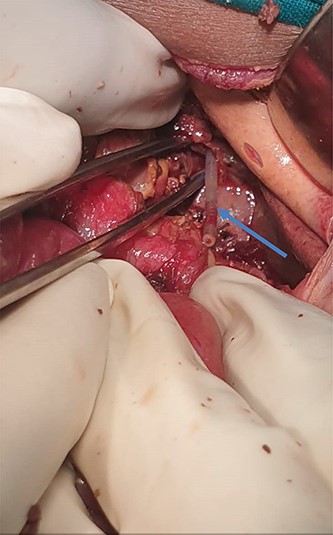

Nasogastric tube was vivid seen within the peritoneal cavity, exiting from abdominal esophagus (Fig. 3).

Orogastric tube seen at the abdominal end of the esophagus. (blue arrow).